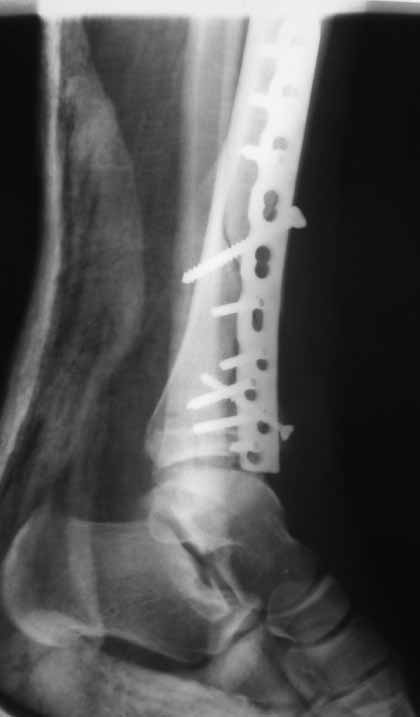

Извиняюсь пропал - оперировал "пилон". В форуме не хотел обсуждать финансовые возможности пациента. Потянул комбинированную пластину. Опыт общение с пластиной "крест" есть - не очень понравилось - слишком много места занимает, даже с учетом обрезаний лишнего. Сделал доступ огибающий медиальную лодыжку спереди. В переднем крае оказался достаточно крупный отломок - удалось зафиксировать винтом. Дефекта кости не оказалось.